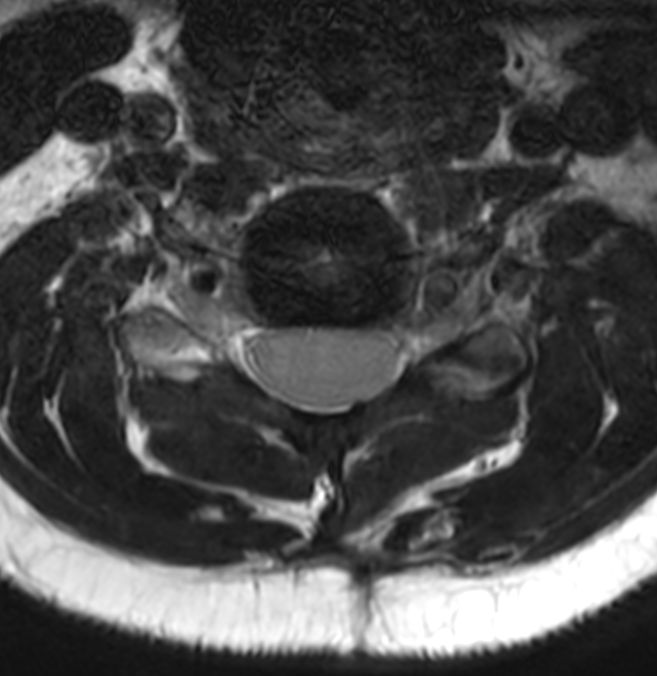

Axial 3D T2w TSE DRIVE